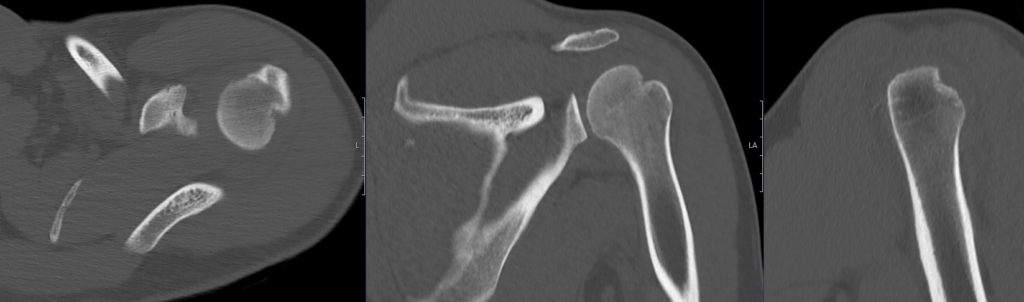

CT Case 104

A 45 year old female presents with shoulder pain following a seizure.

An X-ray of the shoulder found an enlocated shoulder with an irregularity around the glenoid rim.

A CT of the left shoulder is arranged.

Describe and interpret the CT scan

1. Hill-Sachs deformity in the posterior aspect of the humerus.

2. Comminuted displaced osseous (bony) Bankart lesion involving the anterio-inferior glenoid fossa (6-10 o’clock).

3. Comminuted laterally displaced fracture of the coracoid process.

4. Associated joint effusion and surrounding soft tissue haematoma.